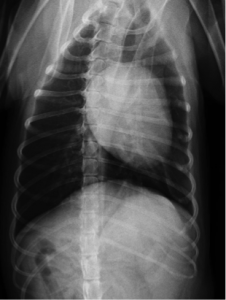

術前レントゲン

明らかな肺転移像はありませんでした